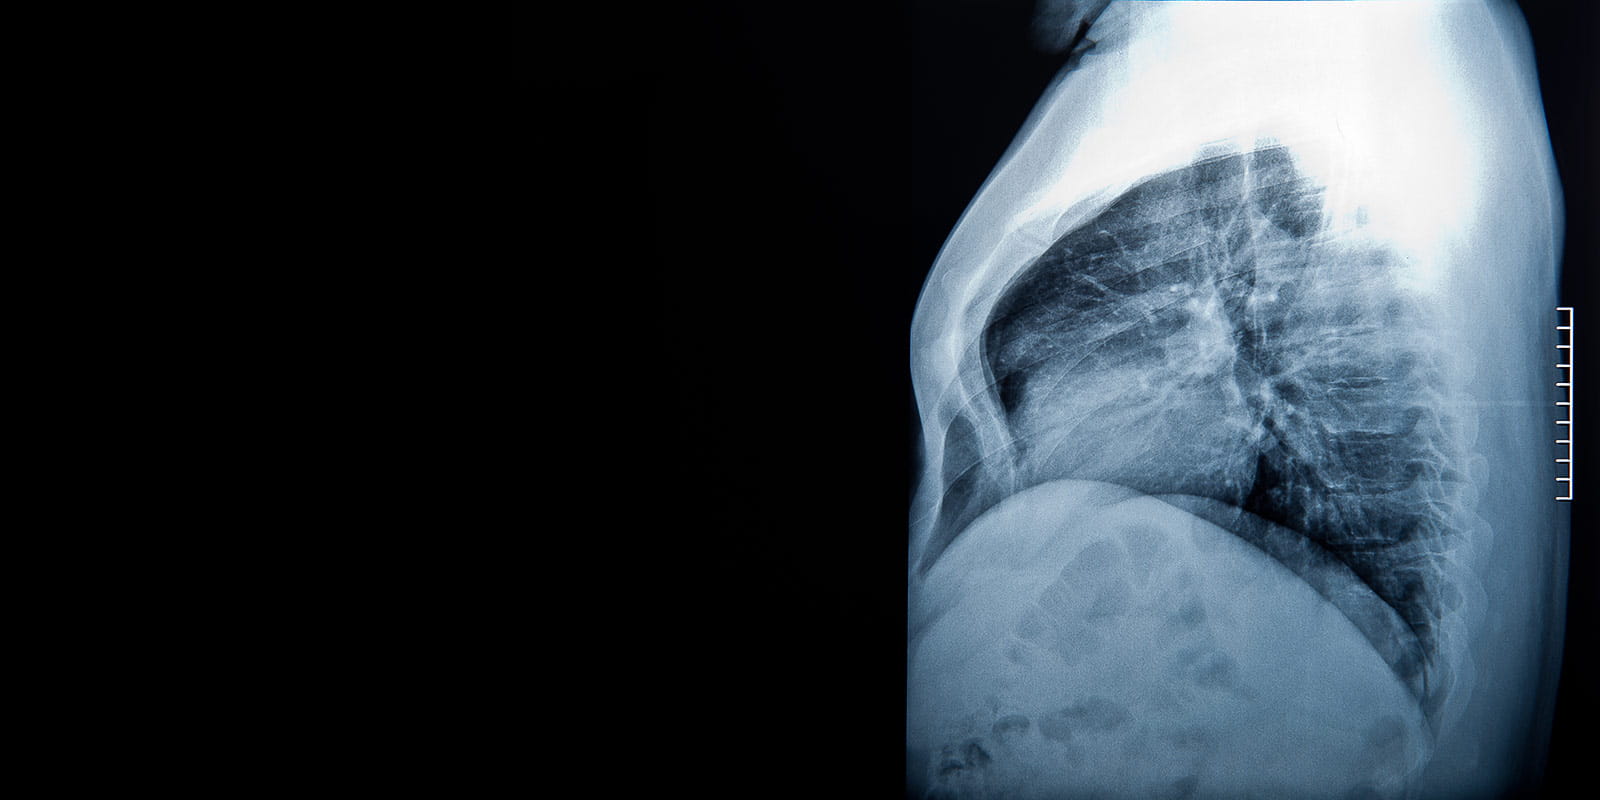

A lateral projection x-rays of lungs and heart shadow, the chest shows a deformity called "pectus excavatum"

Congenital Chest Wall Surgery

We treat congenital chest wall abnormalities, including pectus excavatum. While pectus excavatum is often seen as a cosmetic defect, it can have significant impact on patients through compression of the heart. We offer a minimally invasive repair of this defect and innovative pain control measures to shorten post-operation recovery.